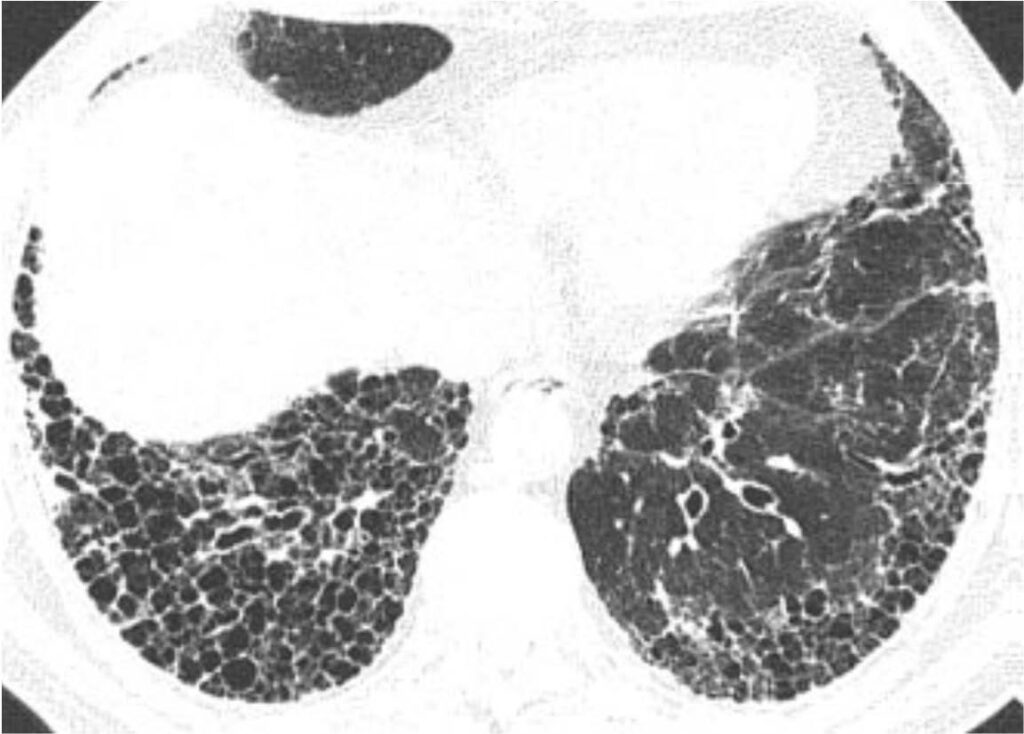

La radiografia del torace (RX) rimane il punto di partenza per la classificazione della sarcoidosi polmonare, utilizzando il sistema di Scadding che divide la malattia in quattro stadi principali sulla base dei reperti linfo-parenchimali.[1, 12, 13]

| IV | Fibrosi polmonare diffusa | Presenza di cicatrici permanenti, perdita di volume e cisti |

Tuttavia, la TC ad alta risoluzione (HRCT) è oggi considerata indispensabile per una migliore caratterizzazione. I segni tipici alla HRCT includono noduli a distribuzione perilinfatica (lungo i setti interlobulari e le scissure), ispessimento dei fasci broncovascolari e opacità a “vetro smerigliato” che riflettono un’alveolite granulomatosa attiva.